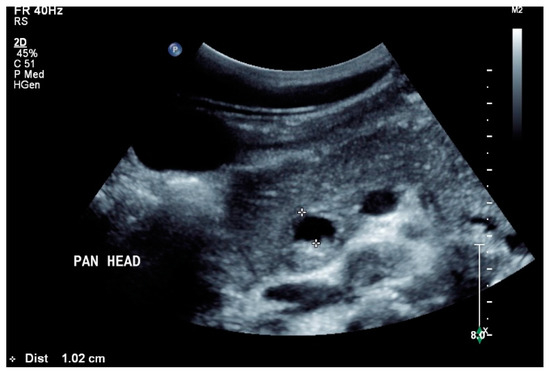

Figure 5.

Pancreatic tuberculosis. Plump large pancreas. There is a lesion with a thick echogenic capsule and hyperechogenic and anechoic contents (between the markers) at the head of the pancreas. This finding was evaluated as a caseous abscess in a patient with tuberculosis.